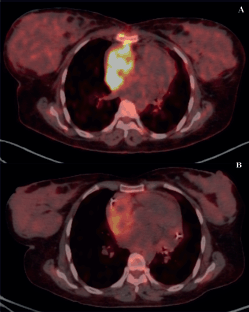

Of 9 evaluable responses (both as first line and subsequent lines) among palliative setting 5 (55.5%) were PR (Figures 3c and 4), 3 (33.3%) were SD and 1 (11.2%) progression. Median progression-free survival (PFS) with systemic therapy was 5.4 months (95% CI: 0–13.7) (Figure 5a). Median overall survival (OS) was 1.2 months (those who did not receive systemic therapy) versus 19.2 months (those who received systemic therapy) (95% CI: 0–42.2) (Figure 5b). The median OS for the entire cohort was 5.1 months (95% CI: 0.2–10.0) (Figure 5c).

Figure 4. PET scans of a patient with locally advanced/unresectable cardiac angiosarcoma (a): Before chemotherapy and (b): After 5 cycles of single-agent gemcitabine.